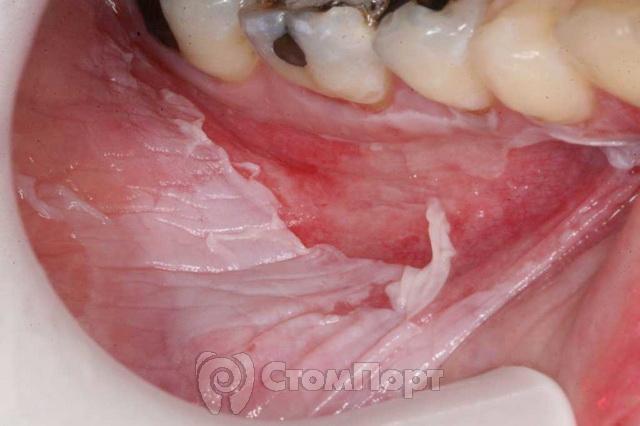

Спиртовий опік відбувається при ковтанні медичного спирту 70-96% і настоянок на основі горілки. Потерпілий втрачає смакові відчуття, відчуває слабкість, біль в області грудей, шиї, шлунка. На стінках стравоходу утворюється білий фібриновий наліт з відмерлих тканин, по вигляду нагадує білок вареного яйця.

Спиртові опіки – найбільш безпечні з хімічних (за винятком пошкодження стравоходу). Спирт утворює плівку на слизовій, що блокує його впровадження в глибокі шари, і сильного ураження, як правило, не виникає.

Під час фарингоскопії, тобто візуального огляду глотки, можна бачити розпушену, почервонілу (гіперемійовану) слизову оболонку; вона нерідко кровоточить, набрякає. Зміни локалізуються на задній стінці глотки, піднебінних мигдаликах, м’якому небі.

При I ступені тяжкості травми переважає гіперемія і набряк, при II ступені картина доповнюється появою нальотів, рідше – бульбашок. Опік III ступеня тягне за собою глибокий некроз, в результаті якого утворюються виразки і струпи.